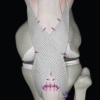

• Đầu dò và giá đỡ kim tích hợp bao gồm một dụng cụ co giãn và kéo dài với một đầu tròn nhẵn, nửa cứng ; đầu kia có tiết diện co giãn để luồn kim cong và chỉ khâu qua ống nhựa.

• Một ống nhựa để lót vỏ bọc của gân bị đứt có vòng chỉ gắn ở đầu ống nhựa, cho phép đầu dò, giá đỡ kim và gân luồn qua vỏ bọc gân từ gần đến xa mà không bị kẹt.